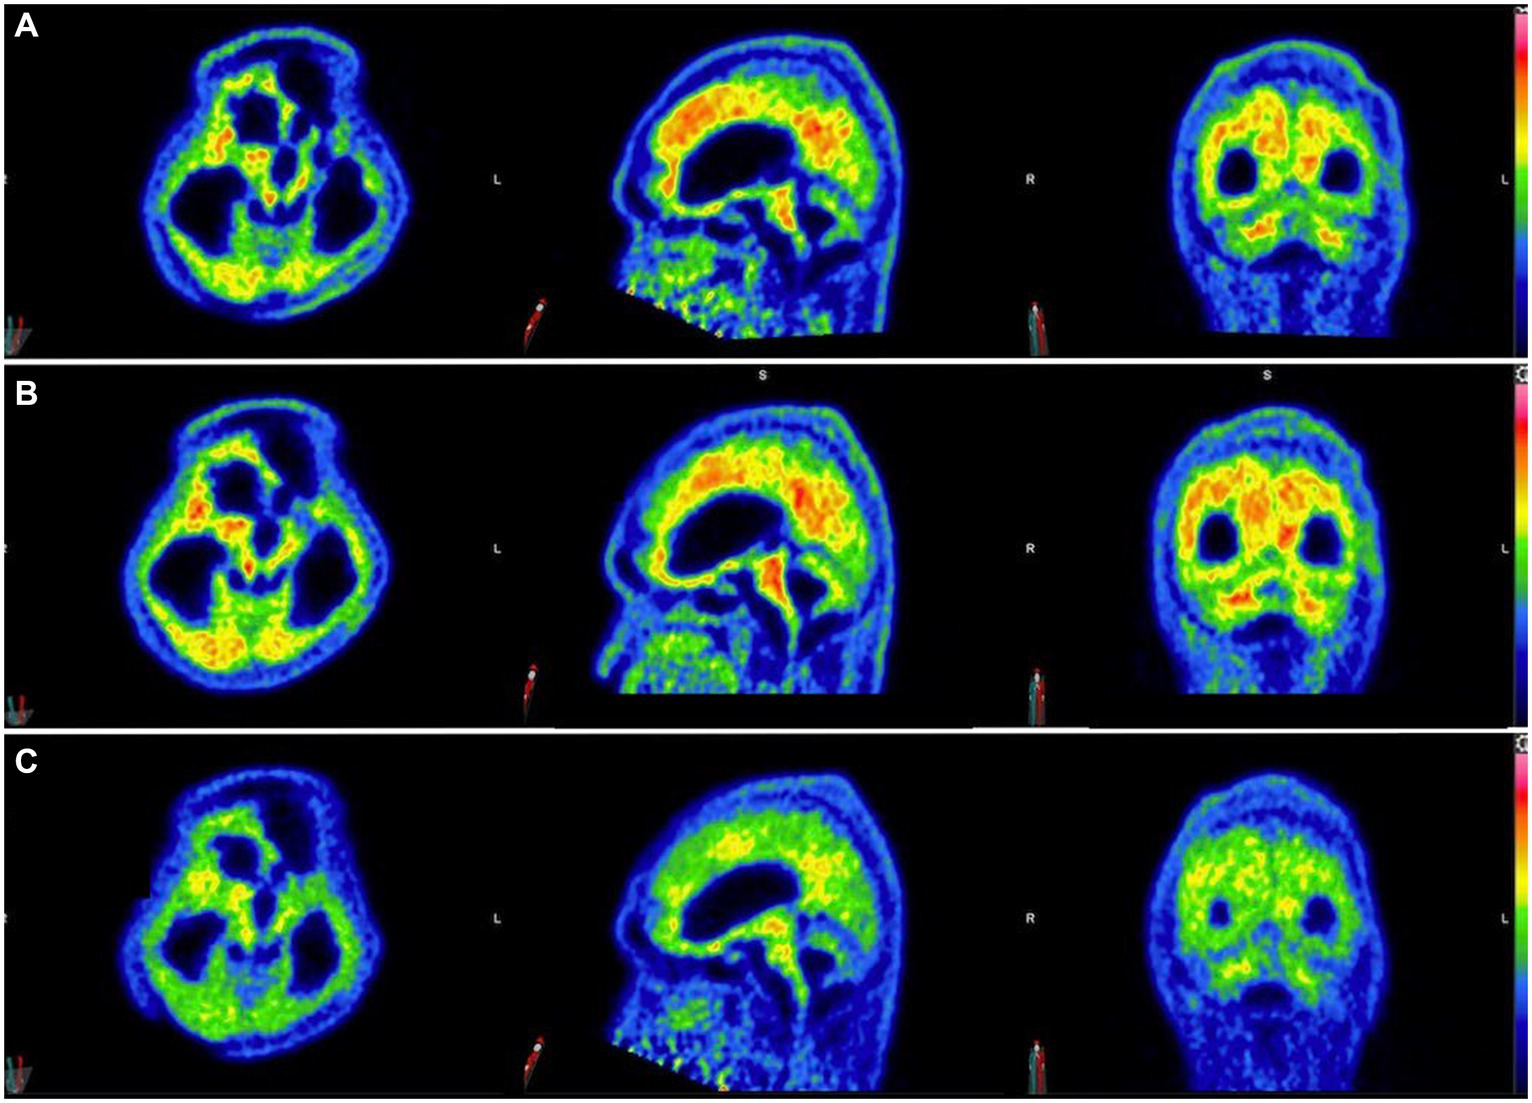

Three 11C-PiB-PET scans were performed at 5-month intervals starting after 6 months of taxifolin administration after the patient was stabilized (Figure 4). Serial scans were arranged to quantify changes in Aβ deposition at 13 regions of interest by determining the cortical-to-cerebellum standardized uptake value ratio of 11C-PiB (SUVR)—in particular, the second 11C-PiB-PET scan revealed a 24% decrease in global Aβ deposition compared to the index 11C-PiB-PET scan, whereas the third scan demonstrated a comparable 22% decrease compared to the index 11C-PiB-PET (Supplementary Table S1). In the first 6 to 10 months after taxifolin administration, a significant decrease in Aβ deposition was noted, as quantified by a 2–77% decrease in the SUVR across all the cortical regions of interest (Supplementary Table S1; Supplementary Figure S2). During this period, the patient experienced clinical improvement in terms of the ability to wean off mechanical ventilation and improved consciousness. He currently requires ongoing neurorehabilitation.

Figure 4

Serial 11C-Pittsburgh compound B positive emission tomography (11C-PiB-PET) scans following taxifolin use. Serial 11C-PiB-PET scans in axial, sagittal, and coronal views followed in response to taxifolin use after 6 months (A), 10 months (B), and 15 months (C), respectively. Visually, amyloid deposition can be gaged according to the colored bar on the right, which corresponds to the cortical-to-cerebellar standardized uptake volume ratio (SUVR; red = high uptake, yellow-green = moderate uptake, blue = least uptake). Note that the semi-quantification parameter cortical-to-cerebellum SUVR is equal to “SUVmean/SUVmean in cerebellum,” where SUVmean is the mean SUV within each cortical volume of interest.

Currently, there is no known effective disease-modifying therapeutic agent to treat CAA. Taxifolin has been well validated in murine models as a potential therapeutic agent for its role in the inhibition of Aβ fibril formation and Aβ disassembly (9–14), Therefore, we decided to use taxifolin only on the grounds of compassionate treatment, as the recurrent lobar ICH was refractory to surgical intervention. The dosing regimen of taxifolin used was determined based on the typical dose used as a dietary supplement. We also present the first attempt at performing radiological semi-quantification of Aβ deposition by utilizing serial 11C-PiB-PET scans. The significant reduction in SUVRs was most pronounced in the cerebellar vermis, mesial temporal lobes, frontal gyri, and thalami (Supplementary Table S1; Supplementary Figure S1). Given that these four regions are known to be involved in executive function, attention, and memory, we postulate that this may explain the partial neurological recovery of the patient, possibly in regaining consciousness (19). It is unknown why there was no further reduction in Aβ deposition beyond 10 months, but it may be because taxifolin dosage was not adjusted, and a plateau effect was established by this timepoint.